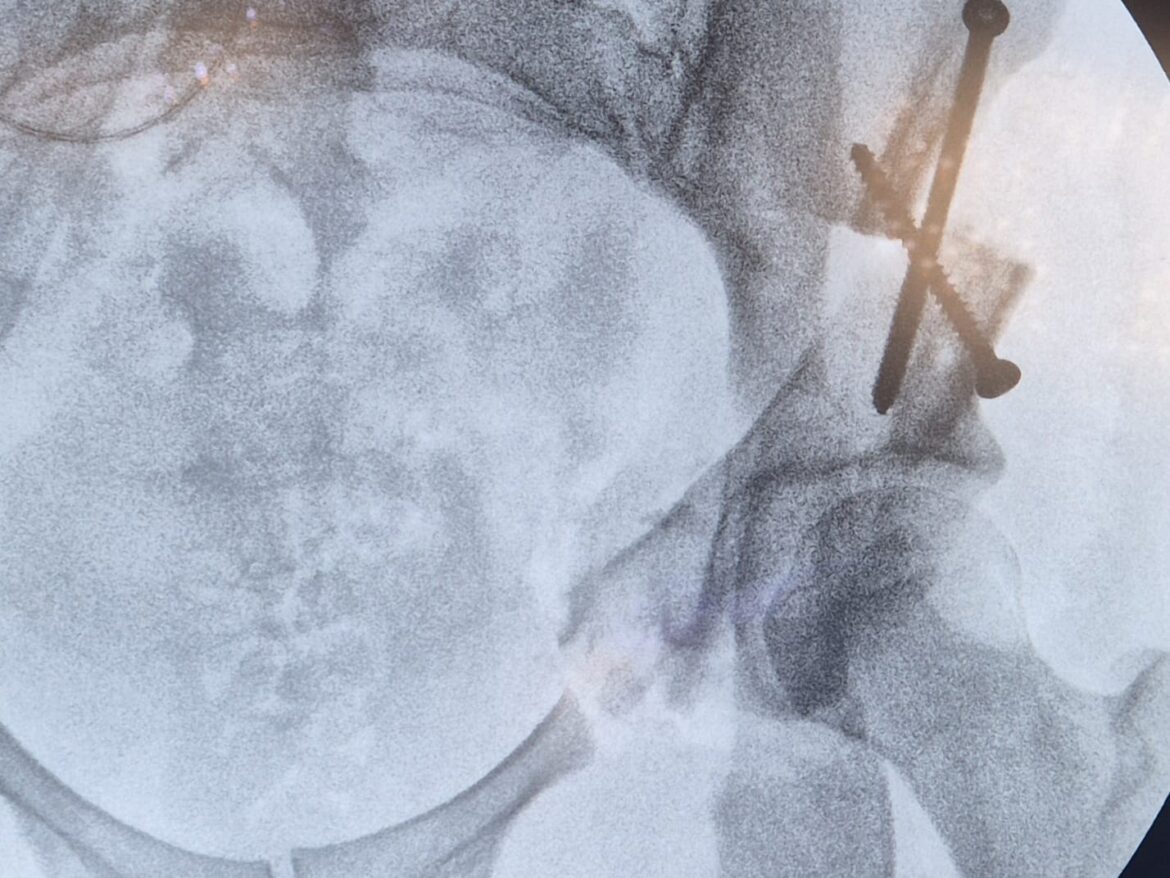

Une attention particulière est portée à la chirurgie mini-invasive, dont l’arthroscopie de la hanche, la prothèse de hanche par voie antérieure, l’arthroscopie du genou, l’arthroscopie de l’épaule et la chirurgie percutanée.

En combinant savoir-faire chirurgical et technologies innovantes, le Dr Majed Issa intervient sur de nombreuses pathologies articulaires. Que ce soit pour une arthroscopie de la hanche, une prothèse de genou personnalisée, ou encore une intervention sur l’épaule, le pied, la cheville, la main ou le poignet, nous mettons en œuvre des techniques précises et adaptées à chaque patient.